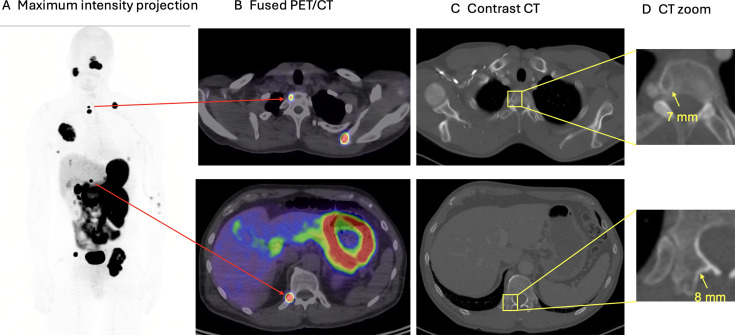

肾细胞癌(RCC)的常规诊断策略主要依赖于超声、CT和MRI。然而,随着几种用于分子成像的新型放射性示踪剂的出现,一种范式正在发生转变。碳酸酐酶IX (CA-IX)成像和sestamibi成像可以帮助识别恶性肾肿瘤,而氟脱氧葡萄糖、前列腺特异性膜抗原和CA-IX示踪剂可以指导RCC的诊断和分期。这些示踪剂可以通过最大限度地减少活检对肾肿块的过度治疗,更好地选择患者进行治疗目的管理,优化低转移性疾病患者的治疗,以及其他新出现的适应症,帮助做出更好的决策。然而,它们都没有被推荐作为标准的临床诊断程序。在这篇综述中,我们探讨了分子影像学检测和分期RCC的最新进展,旨在提高精确诊断和改善患者预后。

Conventional diagnostic strategies for imaging patients with renal cell carcinoma (RCC) have predominantly relied on ultrasonography, CT and MRI. However, a paradigm shift is underway with the emergence of several new radiotracers for molecular imaging. Carbonic anhydrase IX (CA-IX) imaging and sestamibi imaging can assist with identifying malignant renal tumours, whereas fluorodeoxyglucose, prostate-specific membrane antigen and CA-IX tracers can give guidance for diagnosis and staging of RCC. These tracers can assist in enabling better decision-making by minimising overtreatment of renal masses with biopsy, better selecting patients for curative-intented management and optimising treatment for patients with oligo-metastatic disease, among other emerging indications. However, none of them is yet recommended as a standard clinical diagnostic procedure. In this review, we investigate the latest developments in molecular imaging for detecting and staging RCC, aiming to advance precision diagnosis and improve patient outcomes.